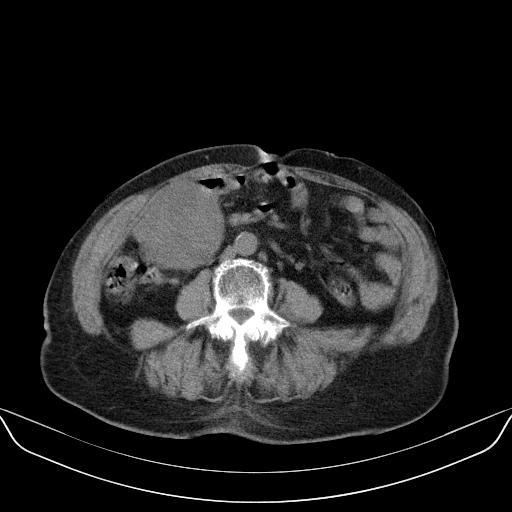

以下是引用林建春在2010-3-11 17:21:00的发言:[br]病变边界较清晰,看见明显包膜,考虑良性占位性病变。[br][br]期待病理结果!

以下是引用yuhongjun在2010-3-12 6:32:00的发言:[br]回肠末端间质瘤,不除外阑尾粘液囊腺瘤,臀部注射性肉芽肿钙化. [br] [br]